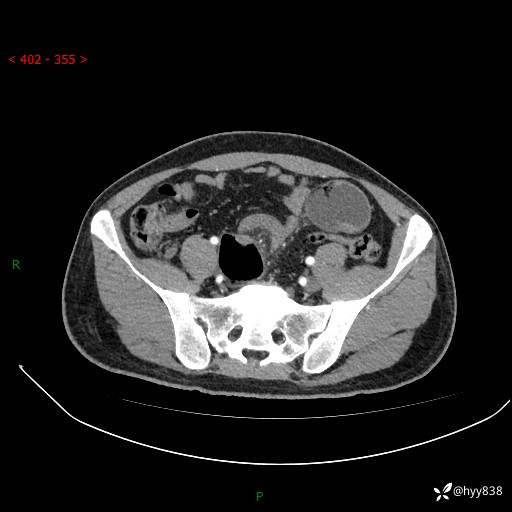

年轻男性,腹痛5月余。除了肠梗阻,你还能看到什么---结果公布~

主诉:腹痛5月余。

现病史:患者于5月前无明显诱因开始出现腹痛,上明显,为间断性胀痛不适,无畏寒发热,无心慌气促等特殊不适,遂来我院。我院门诊遂以“腹痛原因待查”收入我科。 起病以来,患者精神、饮食、睡眠欠佳,大小便正常。体力体重无明显变化。

腹部CT增强扫描(动脉期+静脉期)